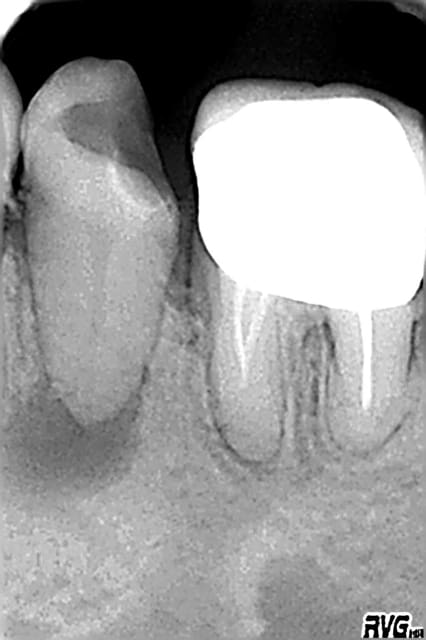

Curieusement je n'ai eu que 3 endos depuis, reprises sur 2 centrales et 1 reprise sur une 26.... 1 a été obturée et les 2 autres sont en cours (durailles les sagouines).

ps: steph comment tu géres la digue et la bague de cuivre.... j'ai dechiré 3 feuilles avant d'abandonner pour la molaire et donc j'ai partiellement desobturé cette fichue 26 mais pas "comme il le faudrait", et j'ai recommandé des boites de digue pasque du coup j'ai épuisé le stock.

ps j'ai bien localisé un mv2 "oublié" par mon predecesseur mais macache pour le cateteriser; comme il semble en continuité anatomique avec le mv1 (y'a comme une fissure qui joint les 2 entrées) j'espere qu'ils fusionnent plus haut car si lors de la prochaine seance je passe pas faudra essayer de noyer tout ça avec l'obturation du mv1.